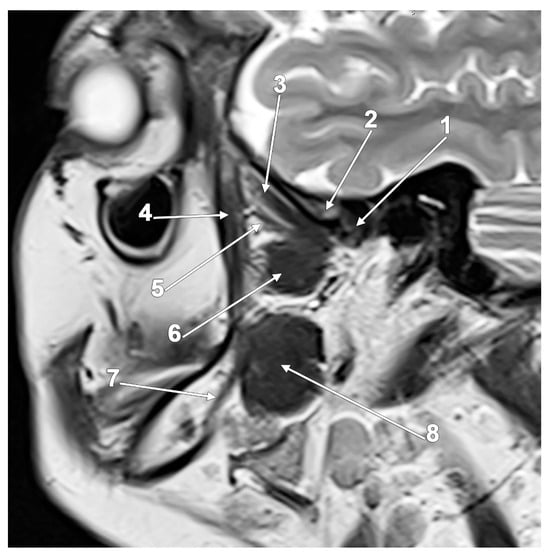

- Mazza, D.; Marini, M.; Impara, L.; Cassetta, M.; Scarpato, P.; Barchetti, F.; Di Paolo, C. Anatomic examination of the upper head of the lateral pterygoid muscle using magnetic resonance imaging and clinical data. J. Craniofacial. Surg. 2009, 20, 1508–1511. [Google Scholar] [CrossRef]

- Dergin, G.; Kilic, C.; Gozneli, R.; Yildirim, D.; Garip, H.; Moroglu, S. Evaluating the correlation between the lateral pterygoid muscle attachment type and internal derangement of the temporomandibular joint with an emphasis on MR imaging findings. J. Craniomaxillofac. Surg. 2012, 40, 459–463. [Google Scholar] [CrossRef]

- Liu, S.; Wang, M.; Ai, T.; Wang, Q.; Wang, R.; Chen, W.; Pan, C.; Zhu, W. In vivo morphological and functional evaluation of the lateral pterygoid muscle: A diffusion tensor imaging study. Br. J. Radiol. 2016, 89, 20160041. [Google Scholar] [CrossRef]

- Litko, M.; Szkutnik, J.; Berger, M.; Rozylo-Kalinowska, I. Correlation between the lateral pterygoid muscle attachment type and temporomandibular joint disc position in magnetic resonance imaging. Dento Maxillo Facial Radiol. 2016, 45, 20160229. [Google Scholar] [CrossRef]

- Imanimoghaddam, M.; Madani, A.S.; Hashemi, E.M. The evaluation of lateral pterygoid muscle pathologic changes and insertion patterns in temporomandibular joints with or without disc displacement using magnetic resonance imaging. Int. J. Oral Maxillofac. Surg. 2013, 42, 1116–1120. [Google Scholar] [CrossRef]